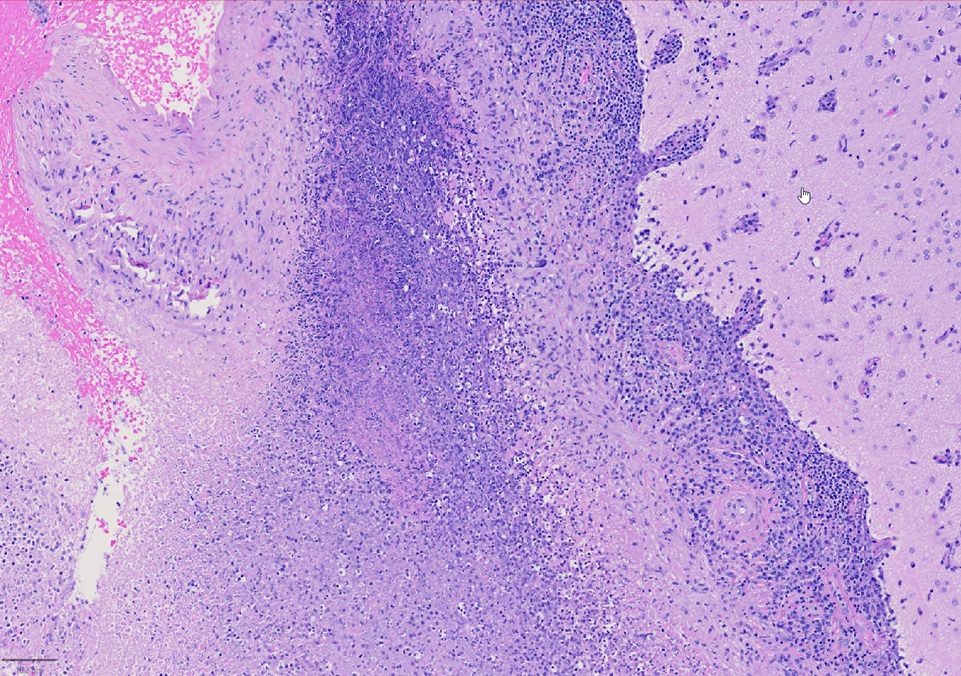

A 79-year-old right handed woman presented to a local hospital with left hemiparesis affecting her upper and lower extremities with mild left facial weakness for the last 2 weeks. She had a longstanding history of RA and had been off immune suppressant therapy for a few months due to improvement in symptoms. She had previously been on methotrexate and adalimumab in the past. She was evaluated with imaging and lumbar puncture (LP) at the time. MRI brain showed a semi-enhancing lesion over the right frontal lobe near the motor cortex with meningeal enhancement (Figure 1). CSF studies showed elevated protein at 65 and pleocytosis with WBC count of 47, 80% lymphocytes. CSF infectious panel was negative, but serum HSV-1 was positive. She reported a cold sore around this time as well. She was treated with broad spectrum antibiotics and acyclovir for 2 weeks. Infectious workup was otherwise negative. She did not have much improvement in her symptoms and was presented to our hospital 3 weeks later. Repeat CSF evaluation showed protein of 70 along with pleocytosis of 33 white blood cell (WBC), 75% lymphocytes. She received treatment with extended broad-spectrum antibiotics for 2 weeks. Rheumatological evaluation was negative for other signs of active RA. EEG showed bitemporal slowing with some quasi-periodic activity over the right temporal regions. She had some left arm shaking as well and was placed on levetiracetam for seizure prophylaxis. She did not have much improvement in her symptoms. A brain biopsy was performed which showed histopathological findings consistent with granulomatous inflammation confirming a diagnosis of RM (Figures 2-4). Labs showed highly elevated rheumatoid factor (RF) (>320) and anti-cyclinolytic citrullinated peptide (CCP) antibodies (>250). Rheumatology was consulted again and recommended high dose therapy with intravenous methylprednisolone for 5 days followed by resumption of immune modulating therapy. She developed a small right frontal ischemic stroke as a resultant of vasculitis from RM which caused exacerbation of left lower extremity weakness (Figure 5). She is kept on aspirin 81 mg daily for maintenance therapy for stroke prevention and levetiracetam for seizure prophylaxis along with daily prednisone and rituximab maintenance therapy for management of her RA / RM from rheumatology. She continues to work with physical therapy for her left hemiparesis which has shown some improvement. She sees rheumatology and neurology for continued follow up.

Figure 4. Necrotizing granulomatous inflammation (rheumatoid nodule) involving leptomeninges.

Histopathological findings eventually determine the diagnosis. In Bathon's assessment, 17 out of 19 victims had RM diagnosed after postmortem. An open brain biopsy was used to make the diagnosis in two cases. Meninges that had swollen nodules or plaques were frequently seen during a physical examination. Rheumatoid nodules, generalized meningeal inflammation, and vasculitis were three aberrant patterns that emerged through microscopic pathological analysis. The majority of the findings (68%) were nodules, which shared histological similarities with subcutaneous rheumatoid nodules. Nodules were seen in the choroid plexus (15%) and the cerebral meninges (92%). The spinal meninges were affected in two patients. The spinal cord or brain parenchyma had no nodules. In 63% of instances, it was discovered that the leptomeninges or pachymeninges had non-specific inflammatory infiltrates with mononuclear cells, primarily plasma cells, and less commonly necrosis and multinucleated giant cells. It is unclear why invading inflammatory cells prefer the meninges—in particular, the dura—to the brain parenchyma. Although brain parenchyma is not a large component of the dura, autoimmune reactions to collagen may be a factor [1]. In 37% of instances, vasculitis was found to have affected the meninges, spinal cord parenchyma, and the brain, as seen in our patient. Lymphocytes and plasma cells were present in the infiltrates of vessel walls. According to the authors, CNS rheumatoid nodules could be regarded as unique to CNS rheumatoid illness. The presence of plasma cells may help to identify CNS rheumatoid illness from other connective tissue disorders like systemic lupus erythematosus (SLE) or Sjögren syndrome in cases of non-specific chronic inflammatory infiltration by vasculitis or meningitis. Rheumatoid nodules are the most typical autopsy findings in people with RA. It is a non-specific inflammatory infiltrate among individuals with biopsy-diagnosed conditions, perhaps as a result of insufficient tissue sample [1,5].